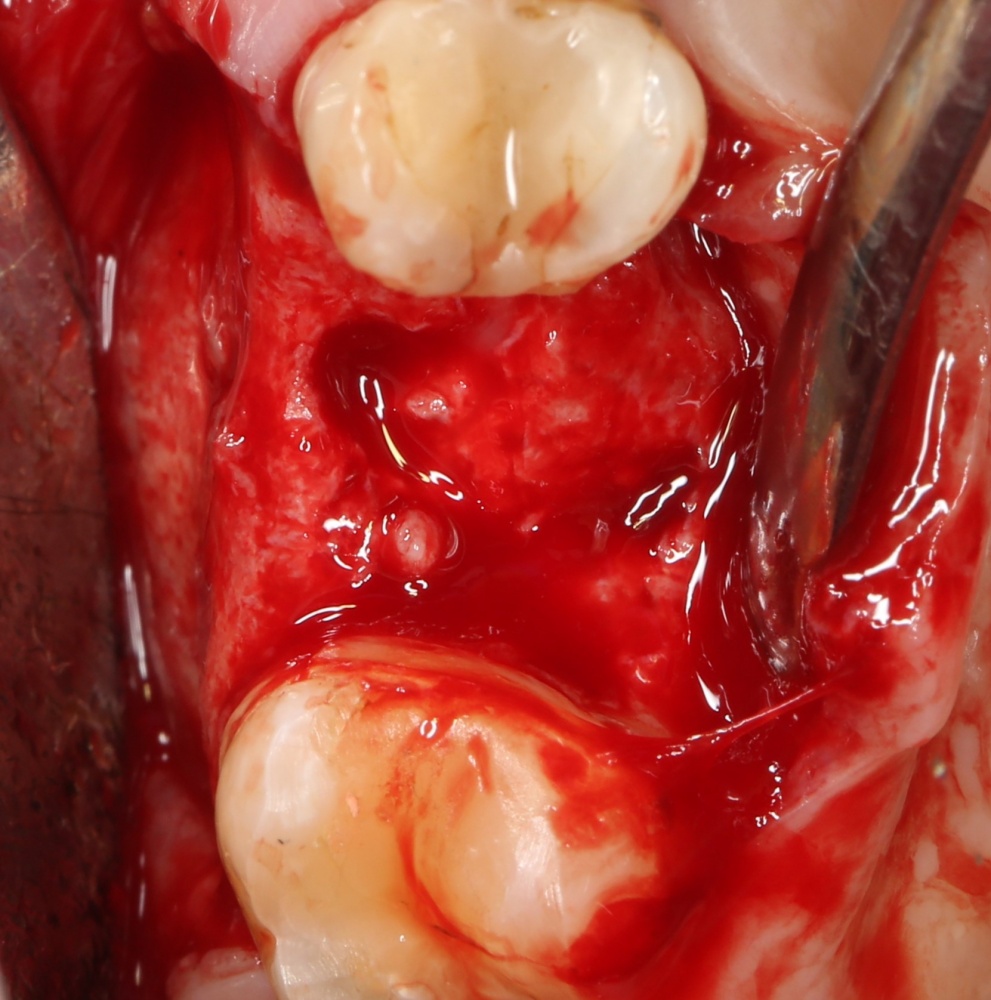

Рекомендации по установке имплантов. Для всех. Часть V.